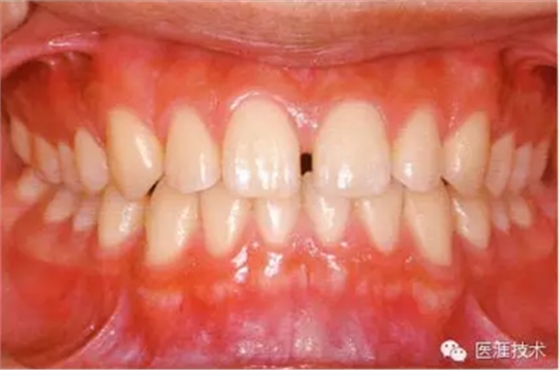

18歲男性的健康口腔內(nèi)部

圖為18歲男性,無特殊全身疾病,不抽煙。持續(xù)保養(yǎng)10年。牙菌斑控制比以前好,因刷牙稍稍過度臉頰側(cè)有牙齦萎縮傾向,但牙齒及牙周組織仍保健康。

28歲女性的健康口腔內(nèi)部

圖為28歲女性,無特殊全身疾病,不抽煙。10年前來院就診保養(yǎng)3年,期間中斷過,現(xiàn)又開始。齲壞風險高,當初初診時已有好幾顆牙的鄰面有填充物,再填充了3牙的鄰面齲,現(xiàn)牙周組織健康。